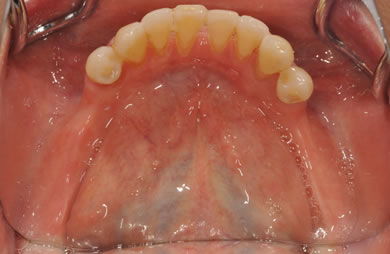

骨再生スピードインプラント治療+AGC連結セラミック治療

| 主訴 | 他院で骨の量が足りずインプラントは難しいと言われ、入れ歯を使用していたが、やはりインプラント治療をうけたい。 | ||||||||||||||||||||||||||||||||

| 治療方針 | 上顎の歯周組織がかなり侵襲されているため、ソケットリフト法にて骨を回復させ、機能的回復だけでなく審美的回復も行うためにAGCハイブリッド連結ブリッジにて補綴処置を行う。 | ||||||||||||||||||||||||||||||||

| 治療内容 | インプラント12本(ソケットリフト+抜歯即日スピードインプラント)、ハイブリッドセラミック8本、AGCハイブリッドセラミック連結ブリッジ1装置、テンポラリーインプラント2本、遊離歯肉移植術 | ||||||||||||||||||||||||||||||||